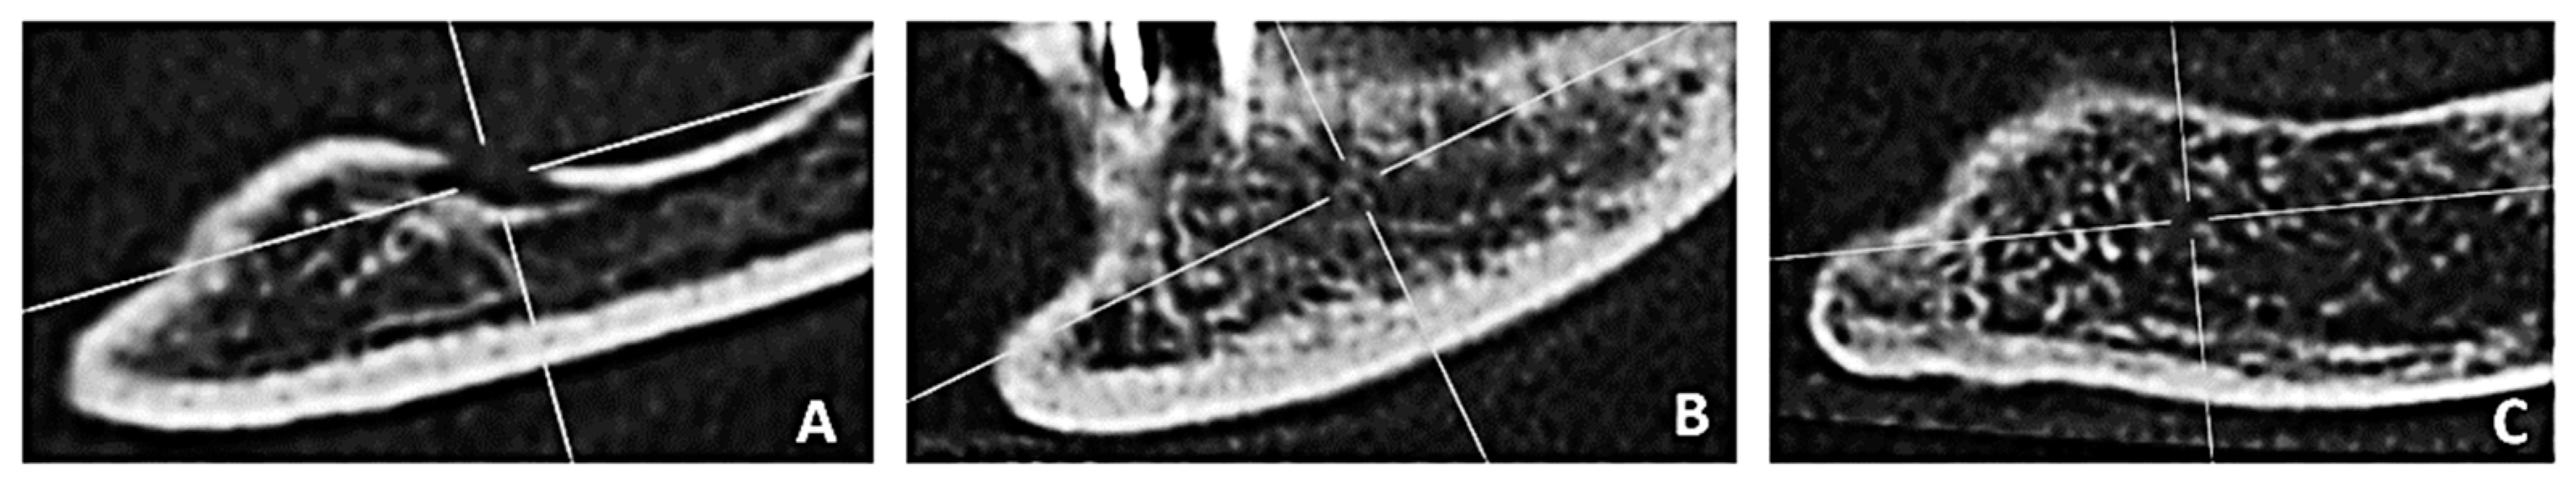

2.3.2. Cortical Bone Thickness

2.3.3. Determination of the Computed Tomography Cortical Index (CTCI)

- C1: the outer edge of the cortical bone is flat and well demarcated;

- C2: the cortical bone layer is characterized by semilunar defects or one to two resorption lacunae;